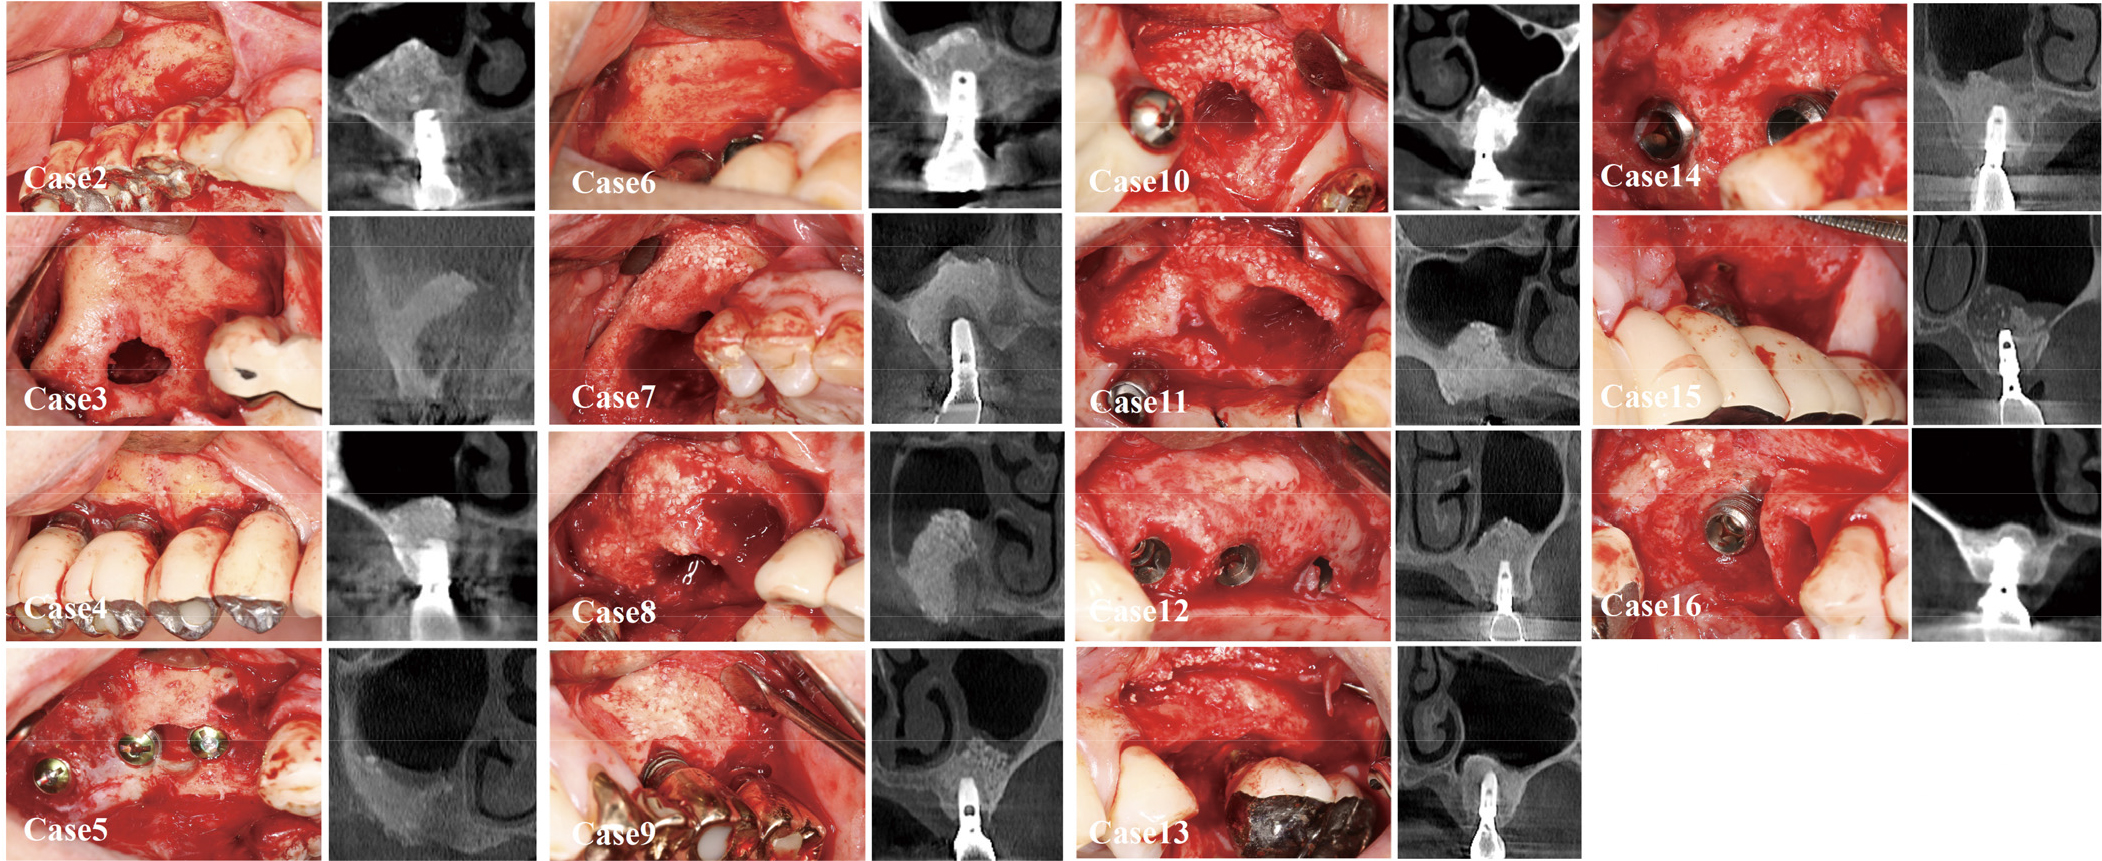

In 16 patients who had undergone lateral MSA, flap surgery was planned in the area where the bony window (from the previous lateral MSA) was neighbored. No barrier membrane was applied to cover the windows for previous MSA. The period between the MSA and the flap surgery ranged from 5 to 27 years (mean: 14.1 ± 7.0 years). Table 1 shows the demographic information of these patients.

For various reasons (peri-implantitis: 11; loss of osseointegration: one; fixture fracture: one; screw fracture: one; additional implant placement in the adjacent area: one; delayed visit for uncovering: one), flap surgeries were performed at the previous implant sites. Intraoperatively, the bony window areas could be observed clinically and radiographically (Figs. 1C, 1D, and 2). Clinically, no site showed unfavorable tissue characteristics in the previous bony window area, such as fibrotic tissue formation extending into the maxillary sinus. Corticalization within the borders of the window was sufficient in all cases, as judged by probing with a periodontal probe and on cone-beam computed tomography (CBCT). Hard feel was detected by probing, and corticalization was observed on CBCT. At eight of the 16 sites, the outlines of the window could not be discerned from the neighboring area. However, at the other eight sites, partial demarcation (indicating the previous window at the lateral MSA) was observed. The remnants of bone graft particles were observed at seven sites. The particles were attached to the inside of the flap; at other sites, the particles could be discerned but were well-integrated with the regenerated bone tissue. At five sites, the bone contour looked bulged compared to the pre-MSA situation. Osteoplasty was performed in three of these cases.